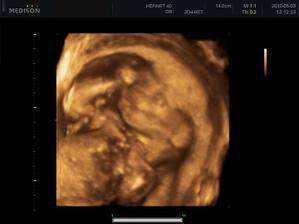

Náš zázrak

autor@didlinka3368 ty by si ju za mňa kľudne aj odrodila, že? Ale najviac sa asi teší budúci tatino.

No to rodenie kľudne nechám na teba, do toho sa nehrniem 🙂, potom si už môžeš robiť čo chceš, ty nám ju len poroď !!! 🙂🙂🙂

Tak dobre OPRAVA - najviac sa teší jej tatino, potom jej mamina aaaaa potom jej druhá mamina - teda JA 🙂